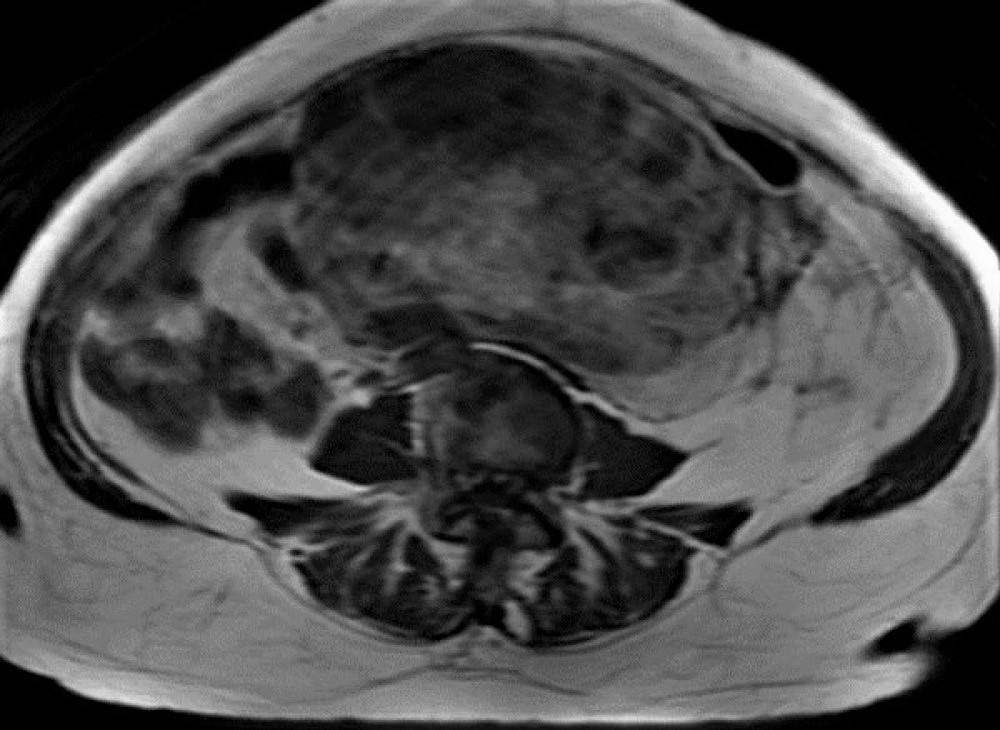

Magnetic resonance (MR) scan of the abdomen and pelvis revealed a large (27.2 cm) retroperitoneal, complex, infiltrative, heterogeneous lesion involving predominantly the mid and left abdominal and pelvic region. Within the mass, there is a circumscribed, complex component with multiple solid heterogeneous nodular foci (Figure 1). The patient had a needle biopsy to establish the diagnosis and subsequently had the mass resected.